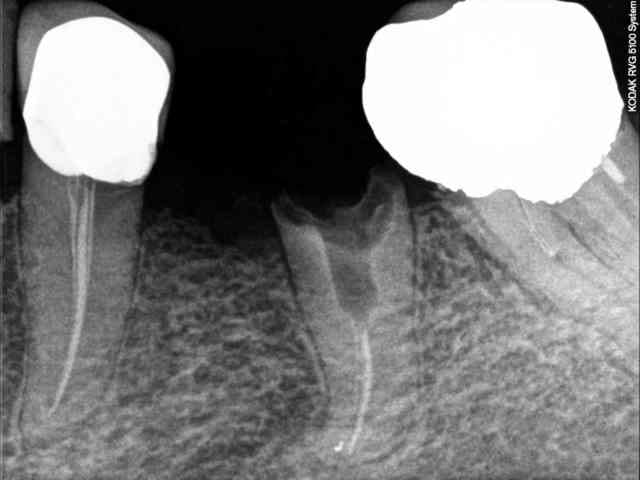

Juste un banal rescellement sur 35?, racine distale de 36 que je n'ai pas fait ce matin pour un combo inlay-core et CCM posé il y a 4 semaines selons les dire de la patiente.

Un peut d'US pour nettoyer la prothèse et légérement la racine, faire un test couronne en place et savoir que quelque soit la solution que j'apporterai, je me ferai emmerder.

Rx1 nljyfz - Eugenol